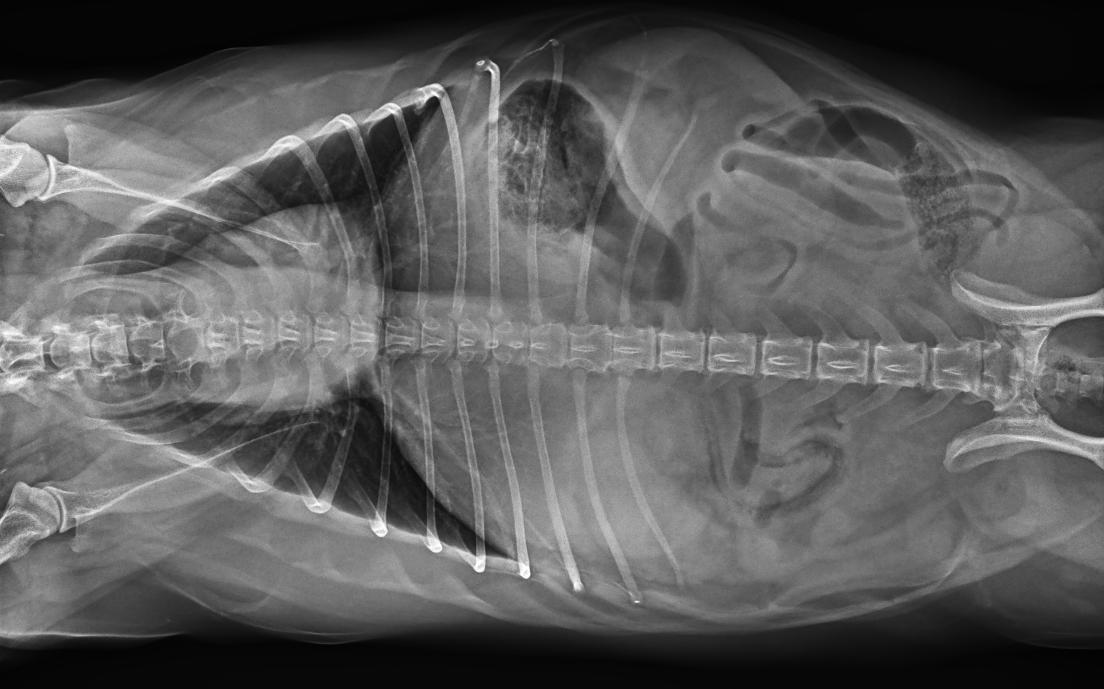

● 17*17大尺寸平板探測器,獲得高質量圖像

● 優異的空間分辨率及信噪比,提升圖像質量

● 采用線噪聲消除技術,使成像質量提升40%

● 智能高效的圖像處理軟件,大幅提升圖像質量